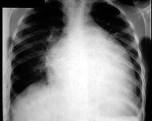

问题 男,24岁,反复胸闷气短4年,近1周加重,端坐时即感胸闷,伴咳嗽、下肢水肿,肝脏肿大。超声心动图示心脏扩大,室壁变薄,EF值20%,二尖瓣、三尖瓣中度反流。胸片如图所示。 患者心功能 ( )

选项 A、NYHA心功能Ⅳ级 B、Killlip分级Ⅱ级 C、NYHA心功能Ⅱ级 D、NYHA心功能Ⅲ级 E、NYHA心功能Ⅰ级

答案 A